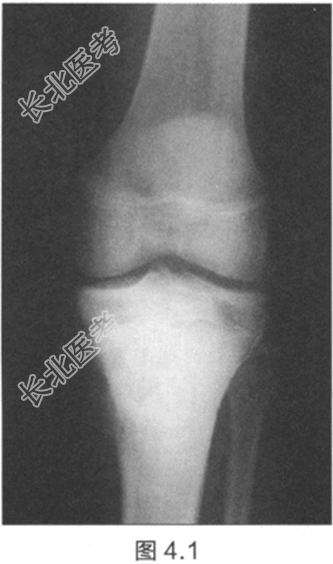

- [材料题] 一名15岁男孩,在度假做日光浴期间,父亲帮忙涂防晒霜时意外发现其小腿上端有肿块。肿块已经出现6个月,并且近期逐渐增大。检查:胫骨近端有一个坚硬、不规则、有压痛的肿块。肿块无疼痛,不影响膝关节活动,其他部位未见肿块。膝关节X线片见图4.1和图4.2。红细胞沉降率(ESR)和血清碱性磷酸酶升高。

- 简答题2、描述一下X线片特征。